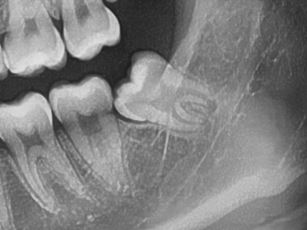

#38,48 사랑니 발치

구강 외과 전문의가 당일 발치했습니다.